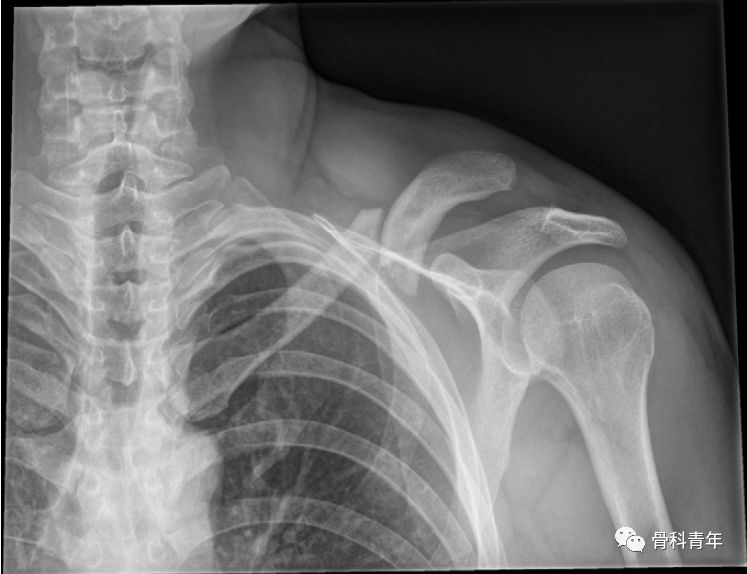

左锁骨骨折合并同侧肩锁关节脱位,采用钩钢板+锁骨钢板固定。